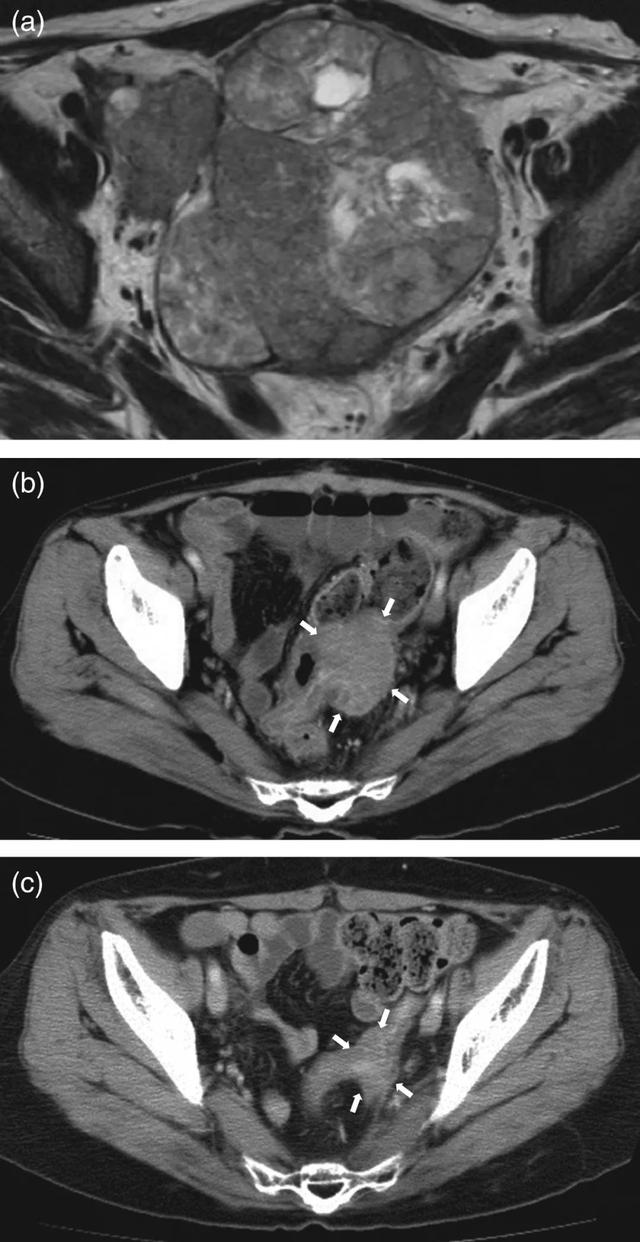

最终,检查结果显示Sutton的卵巢中有一个巨大的肿瘤,已经大到几乎沾满了她的盆腔,并且在主动脉旁和左髂总区还有几处淋巴结转移(CA125值89.0 U / mL)。她被确诊为三期卵巢癌。

本以为一切都已恢复正常的Sutton一家在一年后再次迎来噩耗,复查时发现Sutton的盆腔中有几个多发的肿瘤,病理显示卵巢透明细胞癌,确认癌症复发,其中一个4cm,并且与乙状结肠完全相连,另一个肿瘤大小为2厘米,位于右髂外动脉和右腰大肌之间,根本无法手术,只能接受化疗,遗憾的是,在接受了多柔比星化疗后无效,肿瘤并没有缩小。

(a)术前盆腔被巨大的实体瘤占据。(b)盆腔中复发性肿瘤最大尺寸为5厘米,位于直肠壁的左侧,直肠外侧有肿瘤侵犯。多柔比星化疗后肿瘤的大小没有变化。(c)质子治疗一年后,肿瘤完全消失。